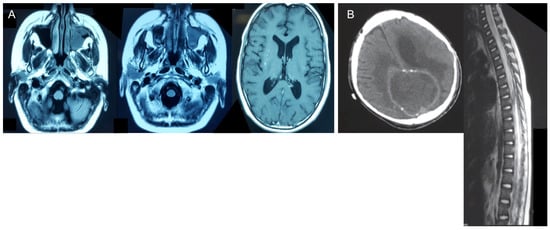

| 1 | yes | yes | yes | proven | yes | no | yes | - | Aspergillus spp. |

| 2 | yes | yes | no | proven | yes | yes | no | no | Absidia spp. |

| 3 | yes | yes | yes | probable | no | no | no | yes | Candida spp. |

| 4 | yes | yes | yes | probable | no | no | yes | yes | Aspergillus spp. |

| 5 | yes | yes | yes | proven | yes | yes | no | no | Mucor spp. |

| 6 | no | yes | no | proven | yes | - | - | - | Candida albicans |

| 7 | yes | yes | yes | proven | yes | yes | - | - | Fusarium oxysporum |

| 8 | yes | yes | no | proven | yes | yes | - | - | Candida albicans |

| 9 | yes | yes | no | proven | yes | no | yes | - | Cryptococcus neoformans |

| 10 | yes | yes | no | probable | no | no | no | yes | Aspergillus spp. |

| 11 | yes | yes | yes | proven | yes | no | - | - | Rhizopus arrhizus |

| 12 | yes | yes | no | proven | yes | - | - | - | Aspergillus spp. |